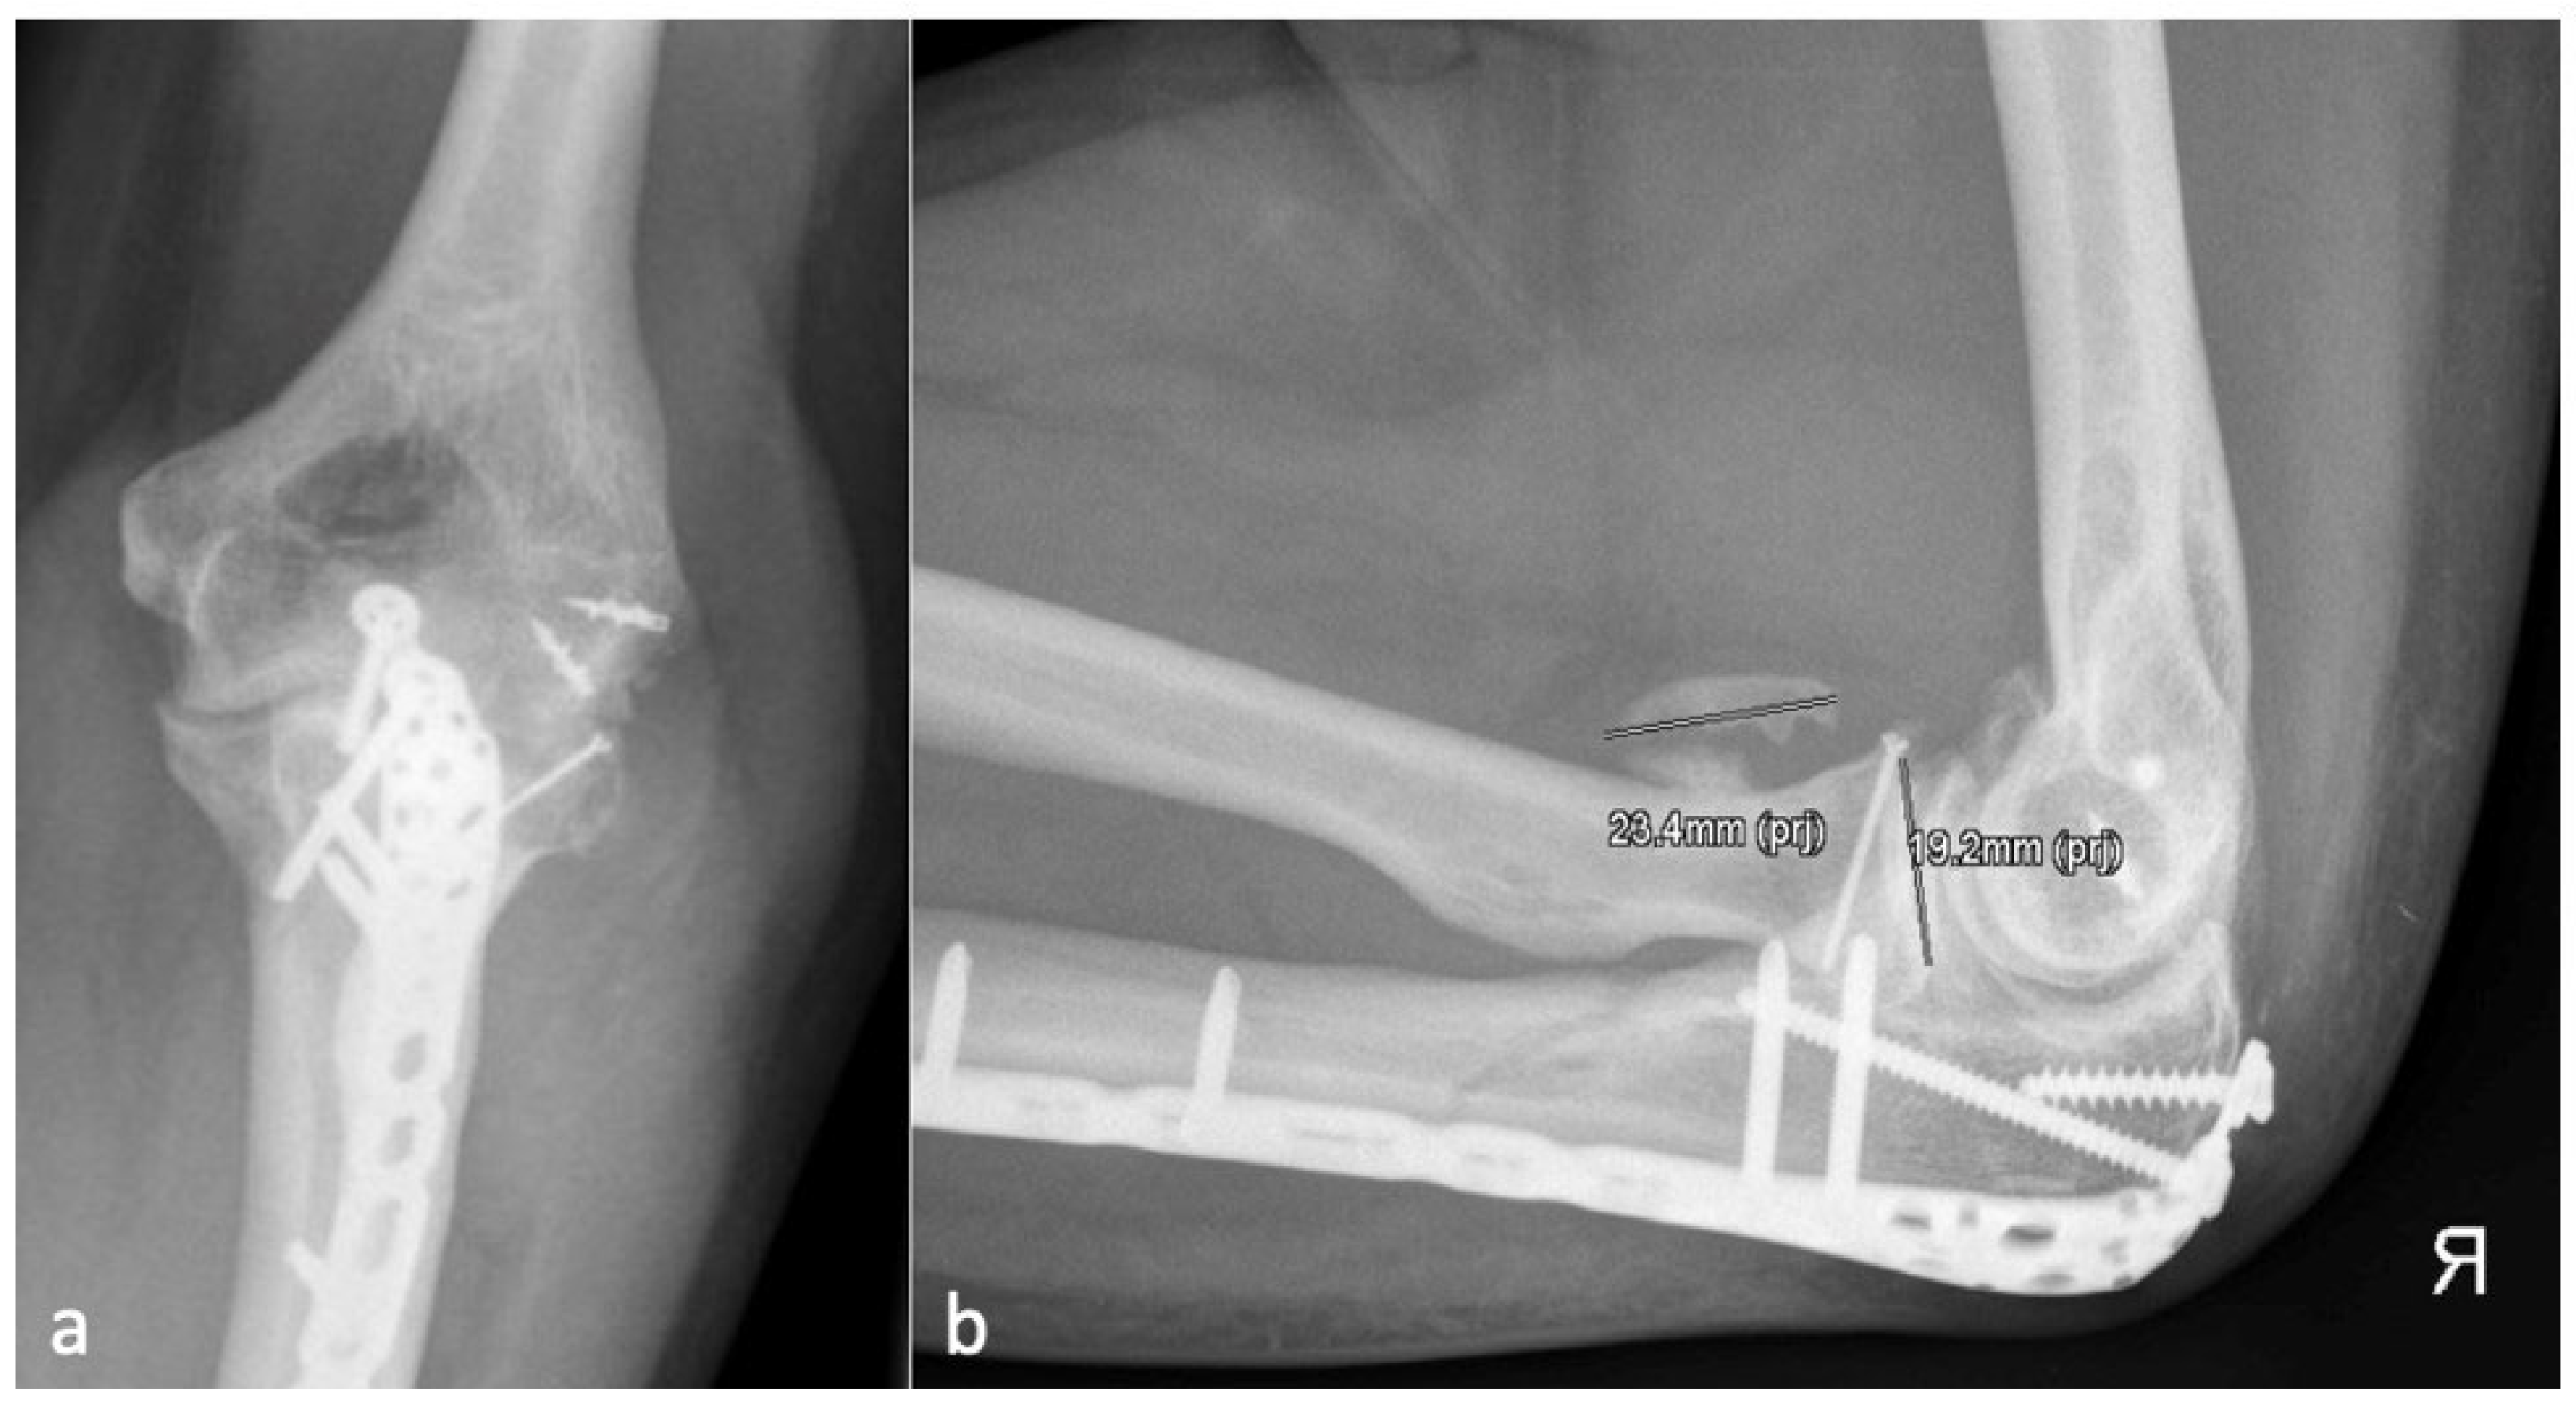

Figure 3.

(a) shows the AP and (b) shows the lateral X-ray with an anterior HO (23.4 mm) which is larger than the diameter of the radial head (19.2 mm) and represents an HO 2a.